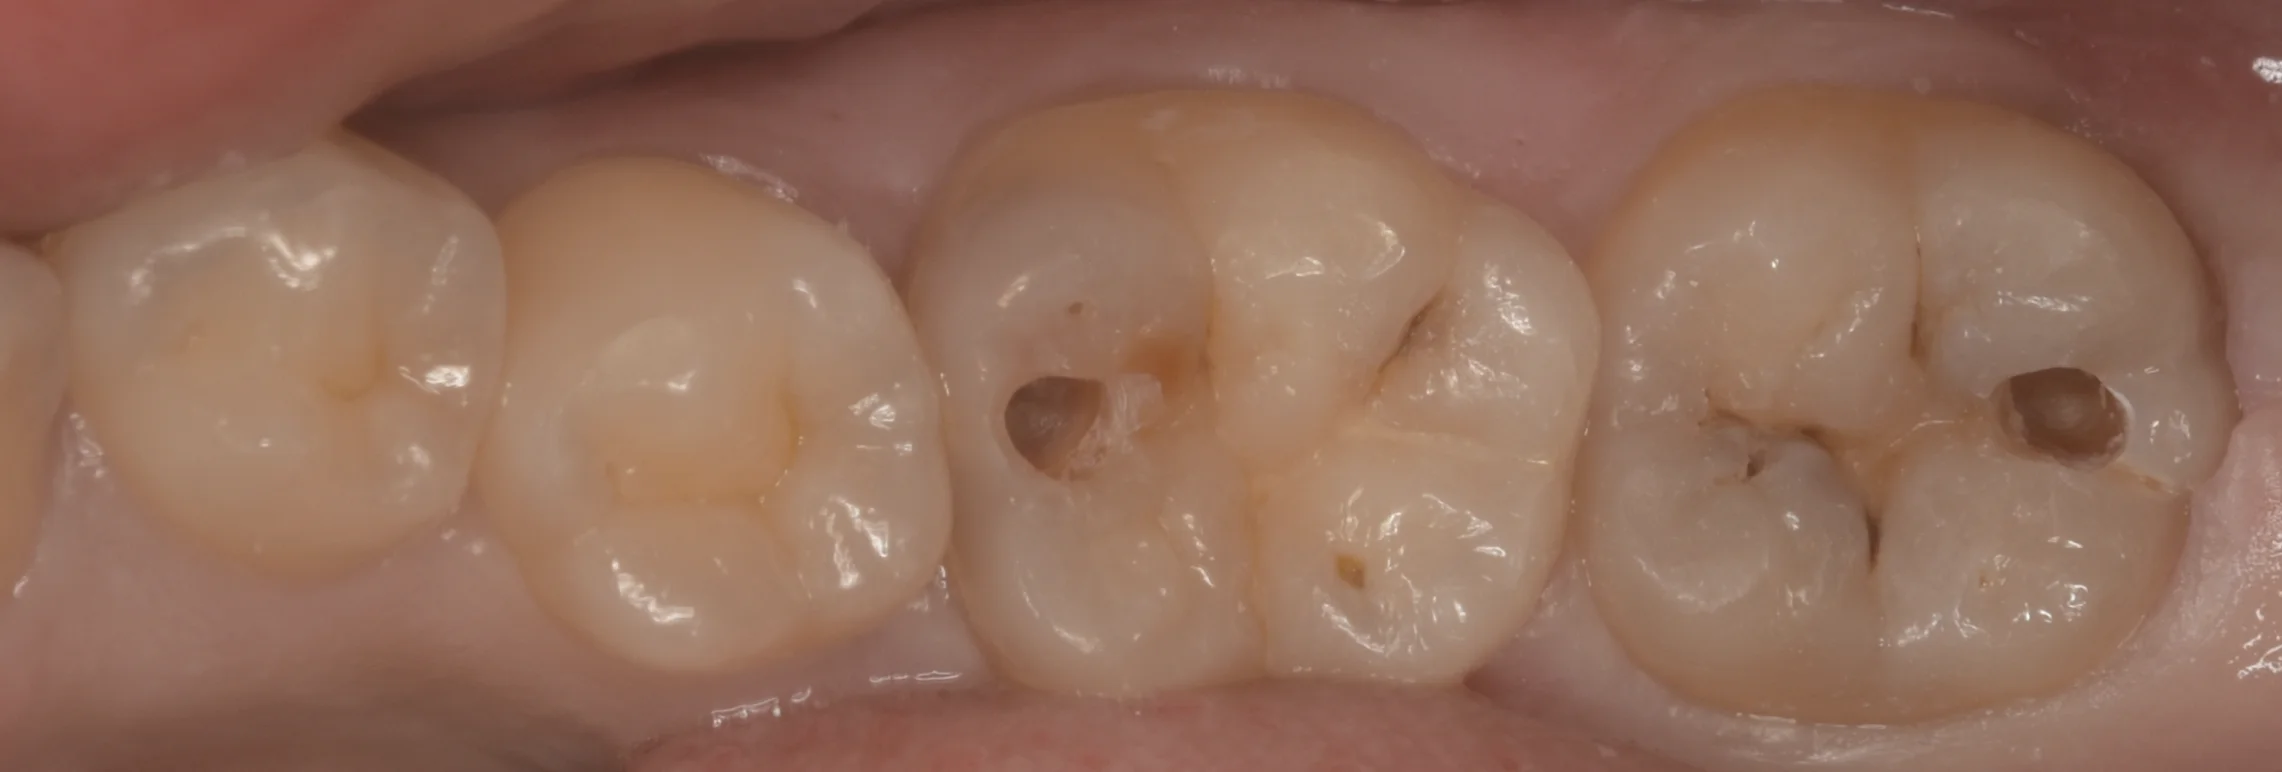

まずは術前からです。

右側2本の治療を行いました。

そのうち、右から2番目は手前の歯側の色が少し変になっているのがわかると思います。

一番右の歯は溝の部分に黒い箇所がいくつかありますね。